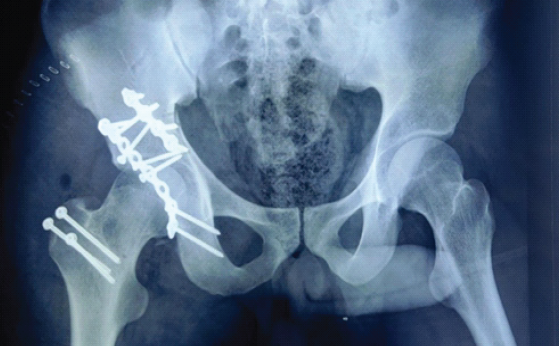

The patient underwent ORIF under general anesthesia using a Kocher-Langenbeck approach. After careful dissection and elevation of the short external rotators, the posterior column and wall fragments were identified, debrided, and reduced. Reduction clamps and traction were used to achieve anatomical restoration of joint congruity, guided by fluoroscopy. Fracture fragments were fixed with reconstruction plates and cortical screws along the posterior column, and supplemental screws stabilized the anterior column (Fig. 3).

Figure 3: Anteroposterior radiograph of the pelvis following open reduction and internal fixation of the acetabular fracture, demonstrating anatomically restored acetabular alignment with stable reconstruction plates and screws along the involved column, and a concentrically reduced hip joint.

Radiographs at 3 months demonstrated consolidation across the fracture lines with stable hardware. At 6 months, the patient walked without aids, reported minimal pain, and had near-normal hip range of motion; the Harris hip score (HHS) measured 87. At 15 months, he reported gradually increasing groin pain, stiffness, and difficulty with prolonged standing and walking. Examination revealed painful limitation of flexion beyond 60°, reduced abduction and internal rotation, and an antalgic gait. Radiographs at 18 months showed femoral-head collapse, subchondral sclerosis, joint-space narrowing, superior migration of the femoral head, and resorption of the superolateral acetabular rim, consistent with Ficat-Arlet stage IV AVN (Fig. 4). Several acetabular screws showed periscrew lucency, indicating loosening. Non-operative measures, including activity modification, non-steroidal anti-inflammatory drugs, and physiotherapy, failed to relieve symptoms. Conversion THR was, therefore, planned.

Figure 4: Anteroposterior radiograph of the pelvis demonstrating Ficat-Arlet stage IV avascular necrosis of the femoral head, with collapse, joint space narrowing, and superior migration.

Conversion THR was performed under combined spinal-epidural anesthesia through the previous Kocher-Langenbeck incision (Fig. 5). Dense scar tissue required meticulous dissection to identify anatomical planes. The sciatic nerve was encased in fibrous tissue posterior to the short external rotators and was carefully exposed and mobilized throughout its course to prevent traction or thermal injury.

Figure 5: Anteroposterior radiograph of the pelvis following total hip arthroplasty, demonstrating a well-positioned uncemented acetabular cup secured with multiple screws and a stable femoral stem, with restoration of hip center, leg length, and overall joint alignment.